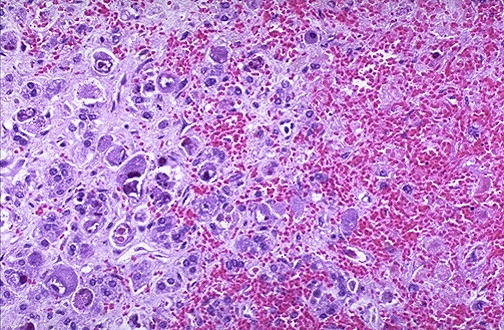

CMV most often involves the adrenal, but this uncommonly leads to major clinical signs or symptoms. Inclusions can appear in medulla and cortex.